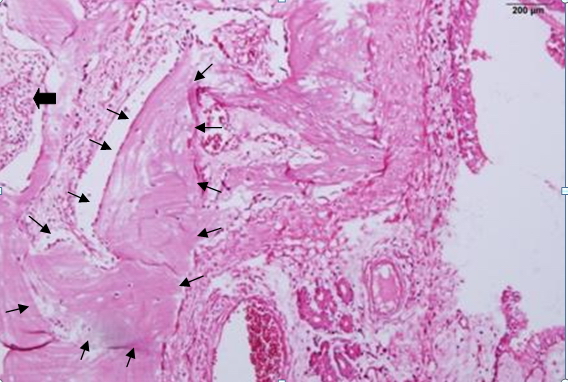

Nasal Polyp With Heterotopic Bone Formation (Osseous Metaplasia): A Case Report

Osseous metaplasia is defined by the presence of heterotopic normal bone tissue in a soft tissue. Metaplastic ossification is a rare event in nasal polyps. The authors describe a rare case of bone formation in nasal polyp of a 28-year-old man with chronic right-sided nasal obstruction without history of trauma or allergy symptoms. To our knowledge, this finding has been reported in a few cases in the English medical literature.